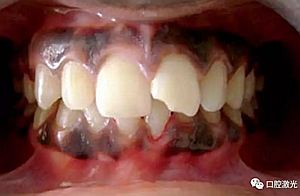

患者22歲,女性,主訴牙齦發(fā)黑??谇粰z查顯示牙齦部位呈黑色,但軟組織健康,沒有表皮粗糙或水腫現(xiàn)象。計(jì)劃使用半導(dǎo)體激光進(jìn)行治療。手術(shù)前患者無需表麻或局麻。采用光纖接觸方式,激光功率設(shè)定為1.5W至2W,連續(xù)模式。氣化黑色牙齦區(qū)域上皮組織。不斷重復(fù)該過程,直至足夠深度的牙齦軟組織表皮被去除干凈?;颊咝g(shù)后需采用漱口水進(jìn)行口腔護(hù)理。

術(shù)中